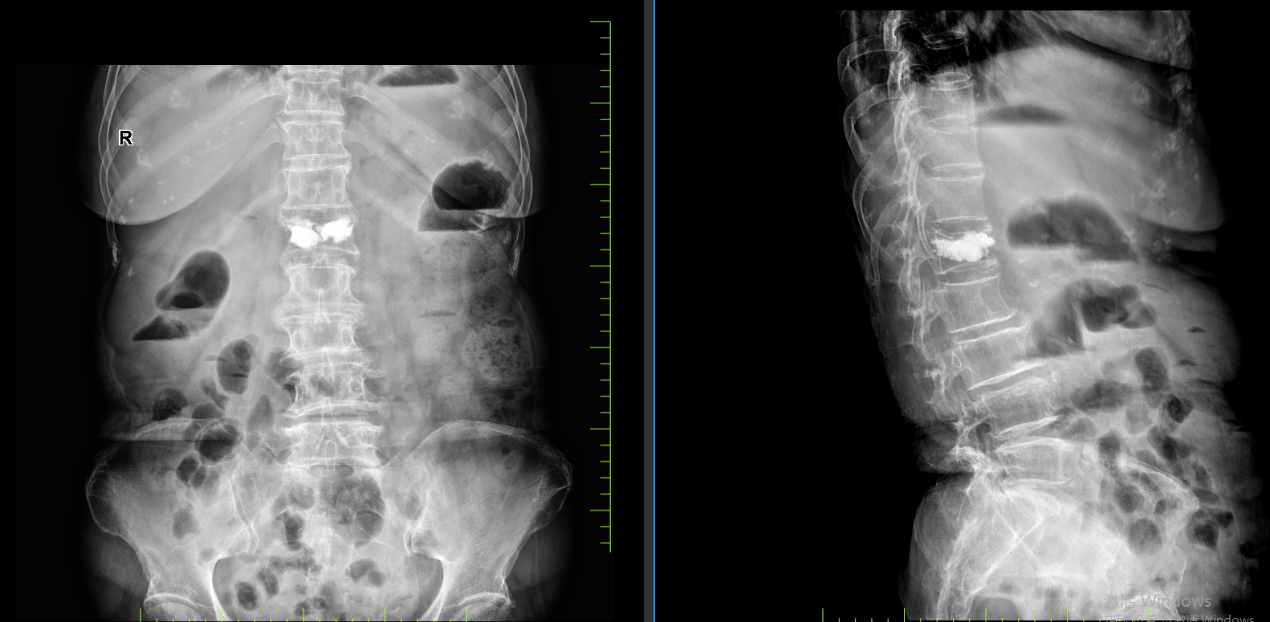

病例三:患者,刘某,女,72岁,因“外伤致腰部及髋部疼痛不适1天”入院。诊断:腰1椎体压缩性骨折,骨质疏松症;行经皮穿刺腰1椎体成形术,手术顺利,术后恢复良好,顺利出院。

腰1椎体压缩性骨 术前X线片 腰1椎体压缩性骨 术前磁共振

腰1椎体压缩性骨 术后X线片